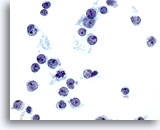

画像 9

肝FNA – 肝硬変

肝硬変結節の良性肝細胞。孤立性に散在しています。核の大小不同がみられますが、核形不整はみられません。二核性の肝細胞が認められ、N/C比は低値を示しています。

40倍

画像 9

肝FNA – 肝硬変

肝硬変結節の良性肝細胞。孤立性に散在しています。核の大小不同がみられますが、核形不整はみられません。二核性の肝細胞が認められ、N/C比は低値を示しています。

40倍